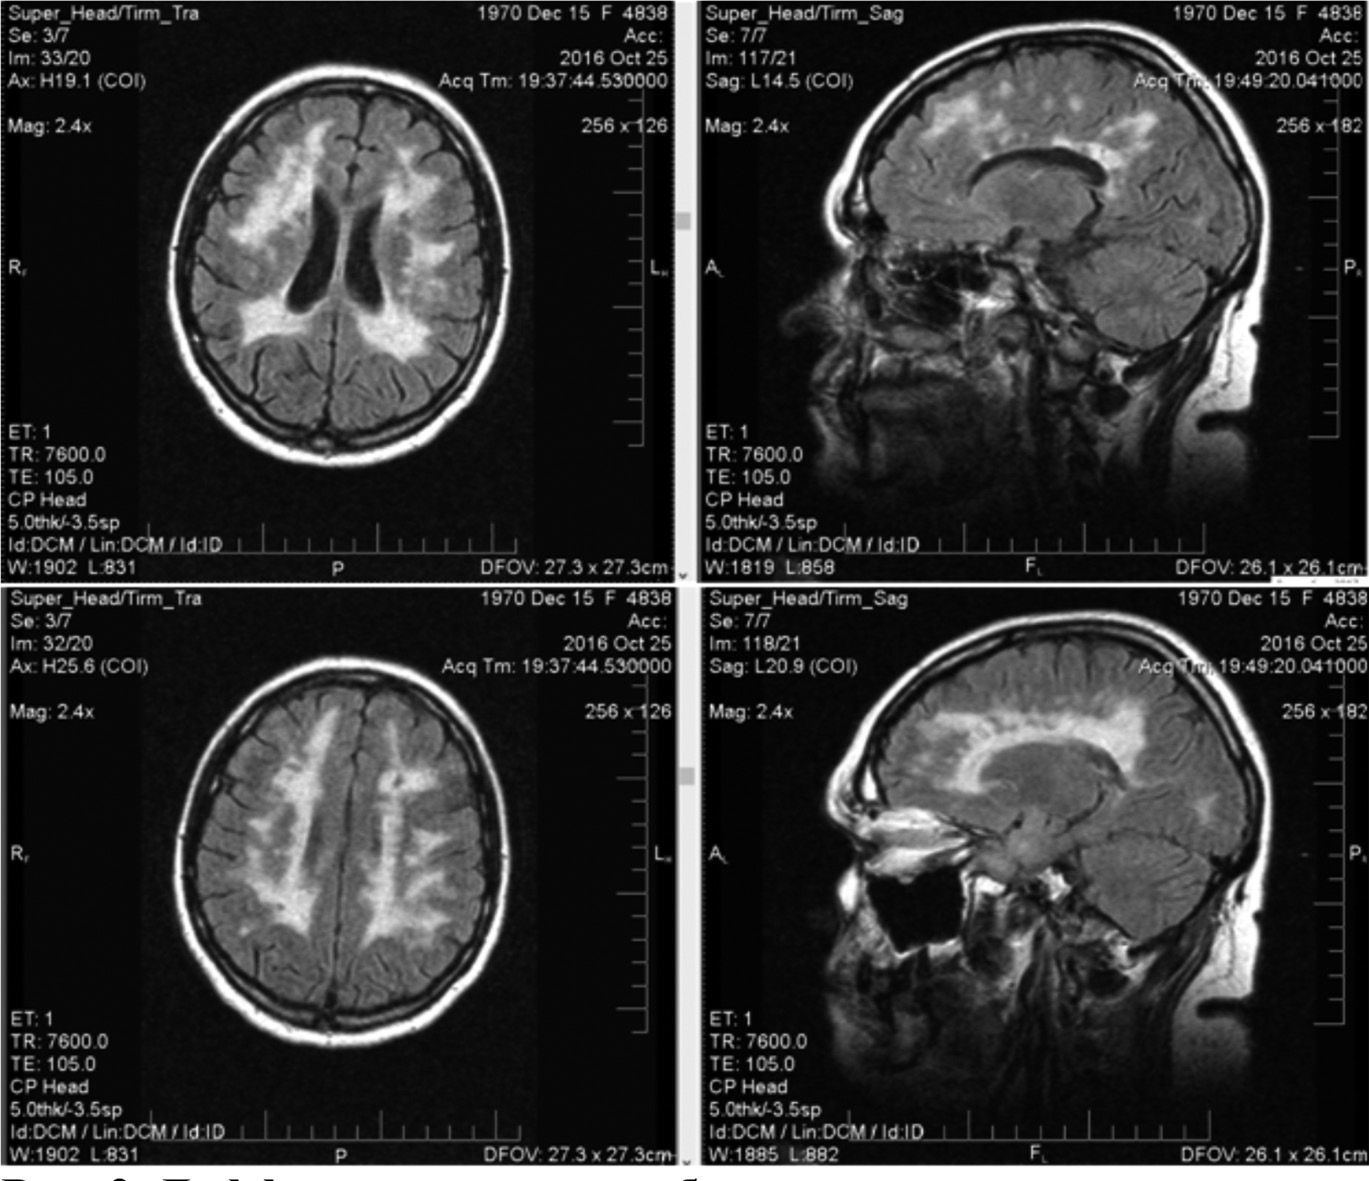

При магнитно-резонансной томографии (МРТ) выявляются симметричные очаги поражения, гиперинтенсивные в Т2 и FLAIR в белом веществе полушарий мозга (рис. 2). Отмечаются также расширение желудочков и атрофия мозолистого тела.

Рис. 2. Диффузное поражение белого вещества у взрослого пациента с CADASIL-синдромом.

Собственное наблюдение авторов. МРТ-картина взрослого представлена как более показательная, у детей сходные изменения на МРТ менее выражены.